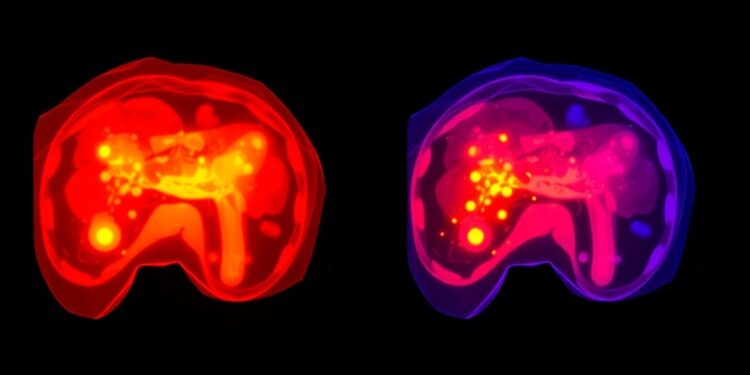

Fluorescence-guided surgery utilizes specific fluorescent dyes to illuminate tumor tissues during surgical procedures, leading to enhanced visualization for the operating surgeon. Among the array of fluorescent agents, indocyanine green (ICG) has garnered significant attention and is frequently employed in FGS. ICG’s molecular structure allows it to bind with plasma proteins, which facilitates its selective absorption by hepatocytes. The unique metabolic pathways of HCC cells reveal a propensity for ICG accumulation due to disrupted biliary excretion mechanisms. This characteristic makes it possible to visualize cancerous tissues during surgery. Yet, despite the utility of ICG, several limitations persist, including its insufficient specificity in distinguishing cancerous from healthy liver tissue, as well as challenges in imaging deeper lesions within the liver anatomy.

Recognizing the drawbacks presented by ICG, researchers are embarking on a journey to develop novel fluorescent probes that may offer more precise and robust tumor detection capabilities. These innovative compounds encompass a variety of mechanisms, including the use of enzymes, reactive oxygen species (ROS), reactive sulfur species (RSS), and pH-sensitive agents. Among these cutting-edge probes, aggregation-induced emission (AIE) probes stand out due to their unique optical properties. AIE probes exhibit minimal fluorescence in dilute solutions; however, they become highly fluorescent when aggregated, which is ideal for applications such as real-time surgical navigation. Several advantages characterize AIE probes: superior biocompatibility ensures minimal toxicity to surrounding tissues, high photostability allows for extended visualization, and reduced background signal interference enhances the clarity of tumor detection.

Clinical endeavors utilizing ICG for fluorescence guidance have demonstrated promising outcomes, facilitating the delineation of tumor borders and enabling the identification of small lesions that would otherwise remain undetectable. Yet, the clinical application of FGS is not devoid of challenges. A significant hurdle arises when attempting to visualize deeper structures due to the limited penetration of near-infrared light, which is crucial for optimal ICG imaging. Moreover, the uptake and distribution of ICG can be significantly influenced by underlying conditions such as liver cirrhosis or variations in hepatic blood flow, all of which complicate its effective use in heterogeneous patient populations. Additionally, benign liver conditions can generate fluorescence signals similar to those from malignant tissue, thereby adding a layer of complexity in accurately differentiating between the two.